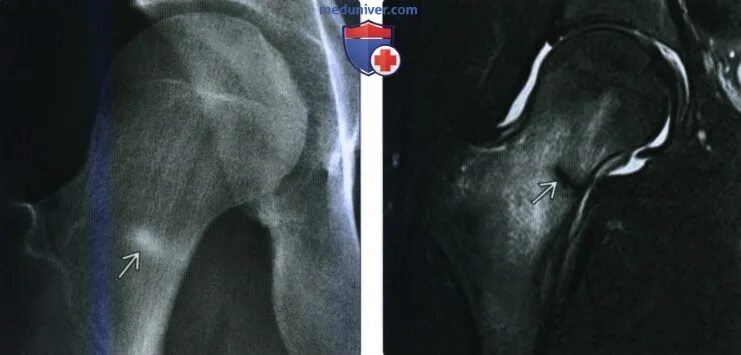

Перелом мрт или кт